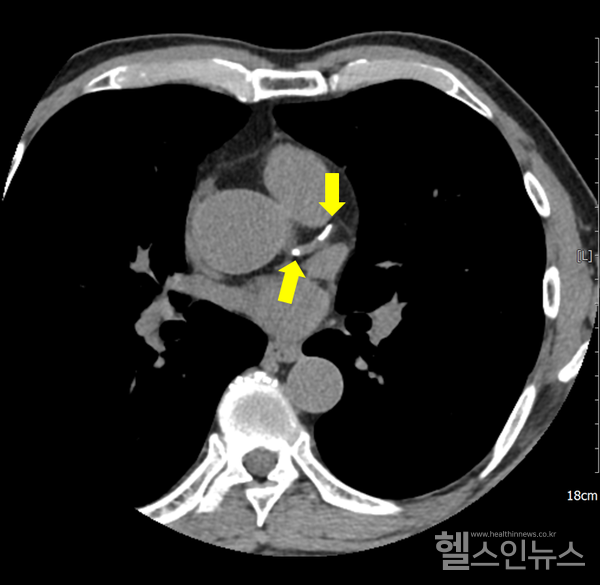

스타틴의 부작용으로는 근육통, 근력 약화, 간 기능 장애, 인지 기능 저하 등이 있으나 실제 임상 경험상 드물고 자가면역 혈관 질환(예: 타우, 동맥염 또는 가와사키병)과 관련이 있는 경우는 드물다. 신장이 제대로 기능하지 않는 경우 지연이나 검사가 필요하지 않을 수 있습니다. 흉통을 인지하고 적절한 치료를 받으면 관상동맥 질환의 위험을 줄일 수 있습니다. 광범위한 손상은 심각한 응급 상황과 만성 심부전으로 이어질 수 있으며, 이는 심장 기능 저하, 고콜레스테롤 및 스타틴 부작용으로 이어집니다. 협심증의 증상은 특히 흉골 전면 바로 아래의 가슴에 압박감, 조임 및 통증이 있습니다. YouTube를 서핑하고 일부를 본 다음 인터넷 검색에 어려움을 겪고 있습니다. 결국 어디 가서 정보를 수집하고 모두가 유명하다는 등 너무 많은 것을 추천합니까? 심장기능, 혈관질환, 석회화, 정도 등을 미리 예측할 수 있습니다. 관상동맥 석회화의 정도는 정상이고 일정 범위를 갖지만 경증, 중증, 중등도 및 고도의 관상동맥 석회화로 나눌 수 있습니다. 손상이 광범위하면 매우 위험한 응급 상황이 될 수 있으며 장기간 반복되면 심부전 및 심장 기능 저하로 이어질 수 있습니다. 수술적 합병증이 있을 수 있으나 심각한 기저질환이 없는 대부분의 환자에게 관상동맥우회술의 위험성은 약물복용 중 안전한 회복과 퇴원이다. 연구팀은 공복혈당과 당화혈색소에 따른 관상동맥석회화 위험도를 발표한 최인영 교수와 장유수 교수의 연구에서 관상동맥 석회화 위험이 1명에서도 증가했다. 당뇨병 이전 수준. 연민 이 상태에 있다면 건강한 생활 방식과 혈압, 혈당 및 콜레스테롤 수치 상승을 방지하는 방법을 실천하십시오. 유투브도 돌아다니고 영상도 보고 웹서핑도 하고. 결국, 모두가 마음으로 정보를 수집하고 유명하든 아니든 너무 많이 추천하고 싶다면 어디로 가야합니까?